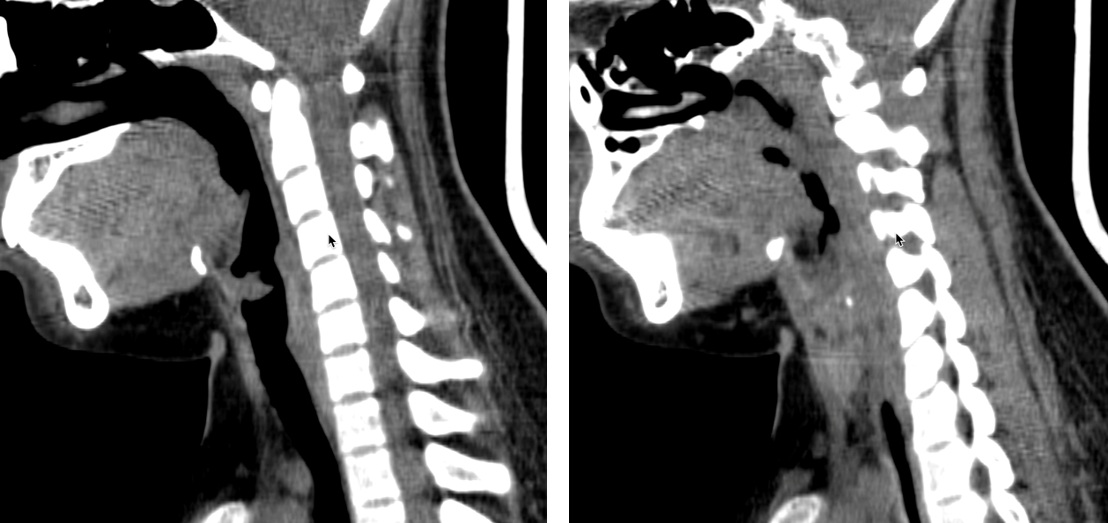

CT scan: Vị trí dây thành âm có cấu trúc đậm độ mô mềm kt # 9*6mm. hạch cổ nhóm II hai bên đường kính trục ngắn <10mm.

Hình 2. Hình ảnh Papilloma trên CT scan